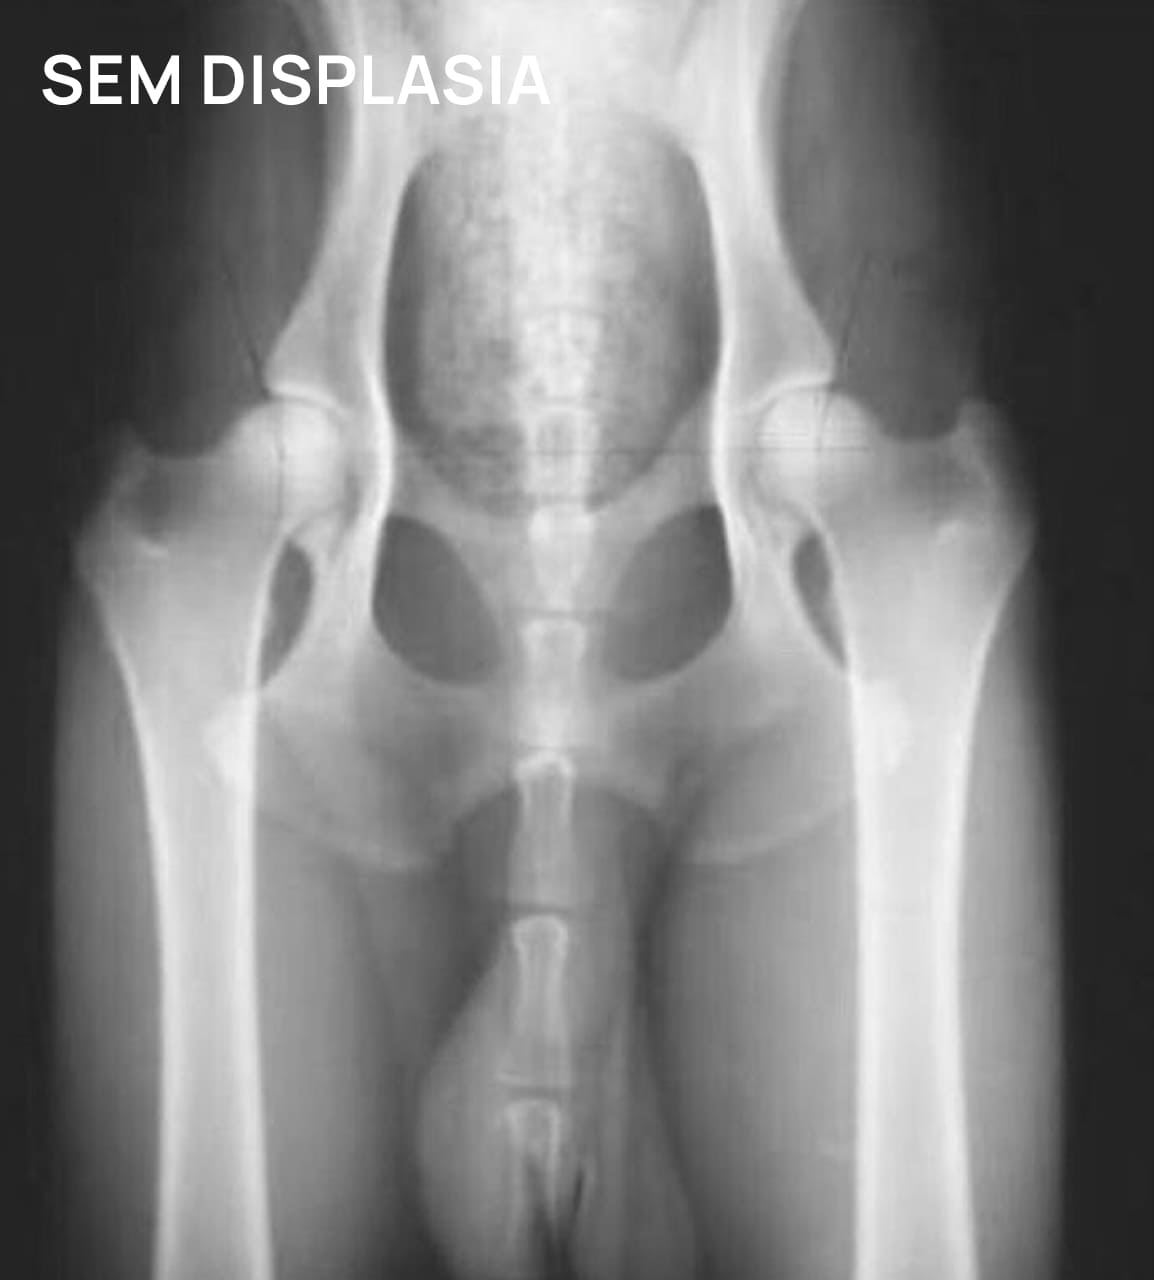

DISPLASIA COXOFEMORAL

A sinais clínicos (DCF) é uma doença de característica genética e poligênica envolvendo uma ou ambas as articulações do quadril, causada pela instabilidade do quadril, levando a incongruência articular e desenvolvimento de osteoartose.

O diagnóstico é baseado na anamnese, exame físico e radiográfico simples. O diagnóstico precoce, em filhotes ainda assintomáticos, pode ser feito por meio do PennHIP, técnica de raio-x por distração articular, que estima o grau de instabilidade do quadril e risco de desenvolvimento de osteoartrose. O diagnóstico precoce possibilita um melhor prognóstico e mais qualidade de vida ao animal.